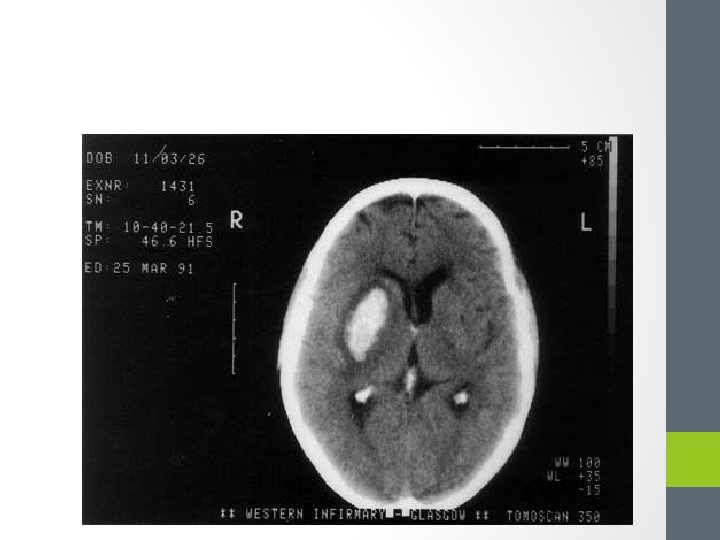

Imagerie • Fait le diagnostic • IRM +++: Diffusion, T 2 Flair, T 2*, 3 DTOF, angio. IRM • TDM: permet le diagnostic d’hématome. Peut être normal à la phase initiale AVC ischémique

• Signes précoces d’ischémie sur le TDM: • • Disparition des sillons corticaux Effet de masse (œdème) Perte de la visibilté des noyaux gris Thrombus hyperdense

Imagerie Le scanner est normal pendant les 6 premières heures!

AVC hémorragique • Saignement intra parenchymateux spontané, parfois associé à un saignement intra ventriculaire • Présentation clinique SIMILAIRE • Un AVC hémorragique peut se présenter sous la forme d’un « AIT » !! • Seule l’imagerie en urgence pose le diagnostic!

• Définition • Constitution d’un hématome intracérébral = environ 15% des AVC • Mécanismes • Rupture artérielle : d’un anévrisme artériel ou d’une MAV • Saignement : d’une tumeur ou d’une métastase • Poussée hypertensive 81